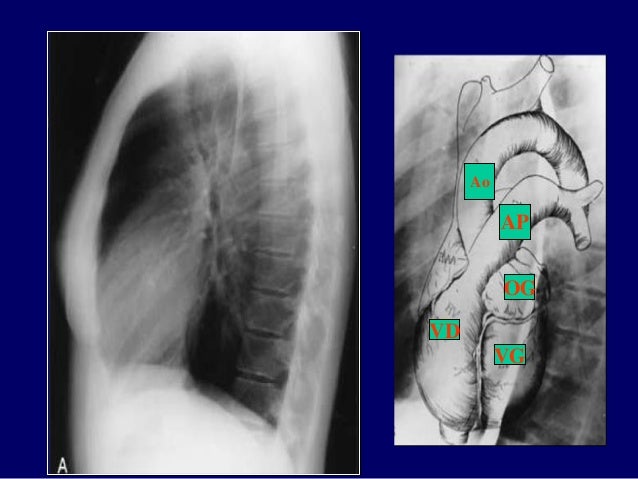

8. 8. Tư thế chụp nằm Tư thế chụp đứng TƯ THẾ CHỤP ĐỨNG

17. 17. OD VD VG Ao AP Ao VD OG VG AP

18. 18. Face VCS OD Ao AP VG Ao VD OG VG Profil OD OG VG VD AP

31. 31. Ao AP VD OG VG

32. 32. Face VCS OD Ao AP VG Ao VD OG VG Profil OD OG VG VD AP

33. 33. Tim và mạch máu trung thất Động mạch chủ lên Tĩnh mạch chủ trên Động mạch phổi Thất phải Động mạch chủ xuống Thất trái